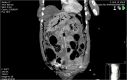

A 91-year-old female presented to the Emergency Department with a 10-day history of constipation and abdominal pain. Abdominal examination was normal and rectal examination showed faecal loading. A phosphate enema was given and the patient was admitted. Overnight, the patient's GCS dropped from 15/15 to 3/15 and an arterial blood gas showed a lactate of 8 mmol/L (1.5 on admission). Abdomen remained soft throughout. A CT scan showed a large amount of free air and free fluid within the abdomen and pelvis, highly suspicious for perforation. Hepatic portal venous gas (HPVG) was visible, with portal venous air fluid levels noted. The patient was treated palliatively and died shortly thereafter. HPVG is a recognized but rarely identified radiological sign, which is a poor prognostic indicator, with most cases subsequently proving terminal, often due to subsequent bowel necrosis.